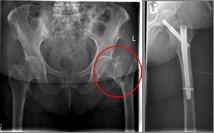

Images: Here is the supply of a dynamic hip screw shown.

In younger patients and a minor shift, the goal is to preserve the femoral head. The blood supply to the femoral head is at risk for medial femoral neck fractures, so that the fastest possible care should be sought if one wants to preserve the femoral head. Among others, the dynamic hip screw (DHS) is available for this purpose.